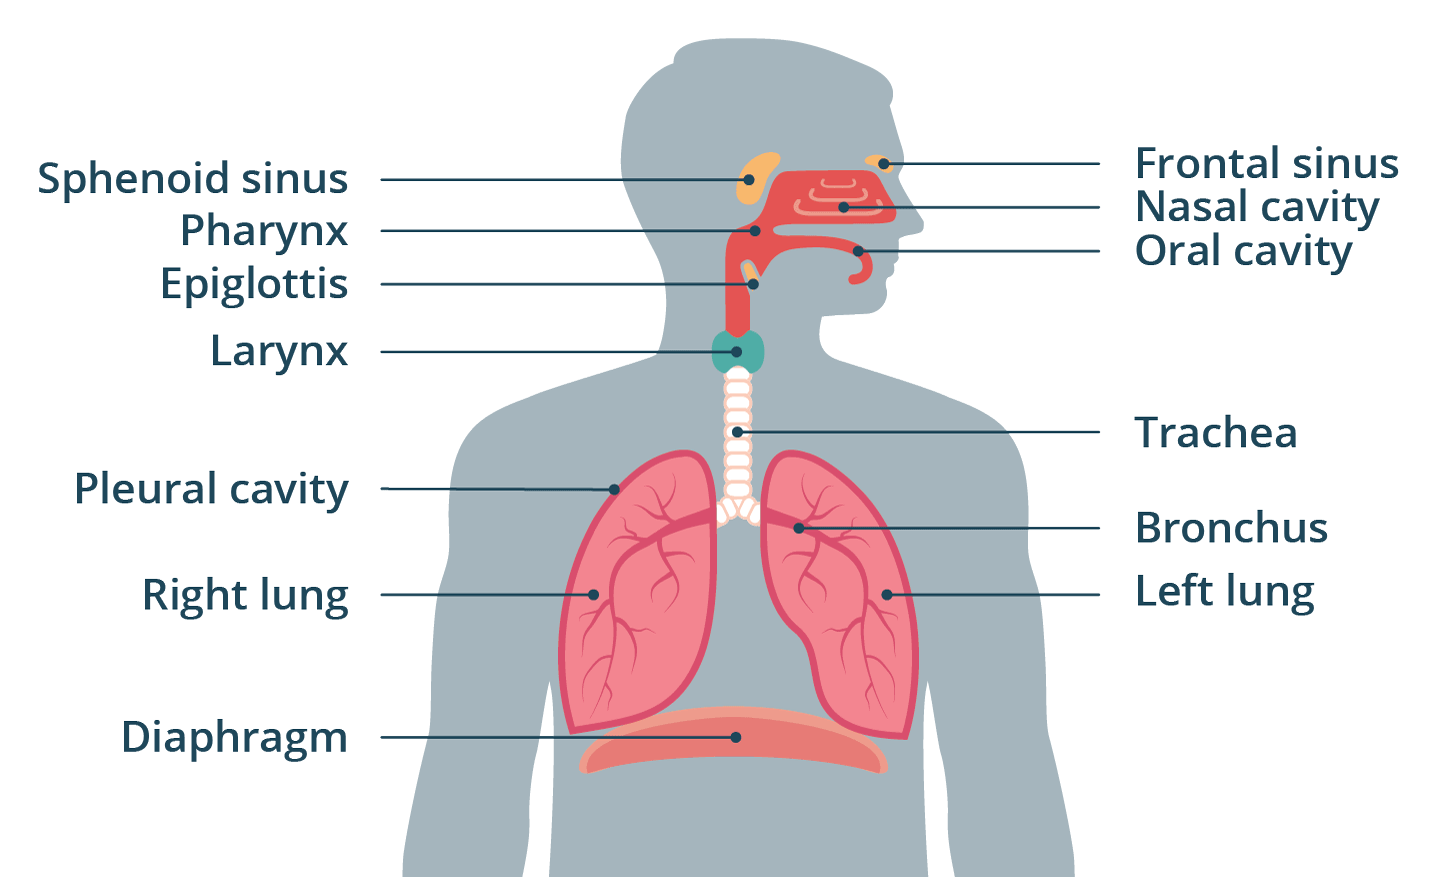

respiratory tract

pleural cavity